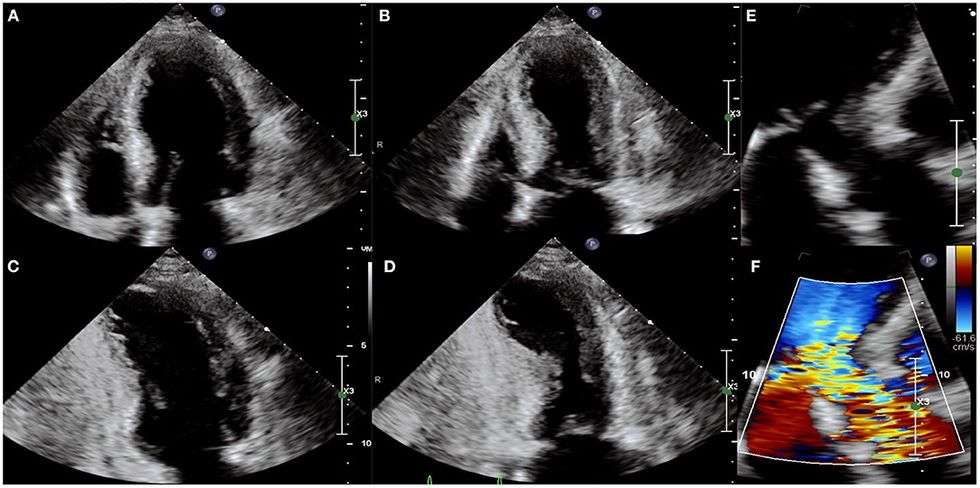

Sipas udhëzimeve të European Society of Cardiology (ESC 2023), diagnoza konfirmohet përfundimisht vetëm pas koronarografisë dhe ekokardiografisë, ku vërehet dobësim i përkohshëm i pjesës së majtë të zemrës (ventrikulit të majtë), shpesh me formën tipike “takotsubo”.